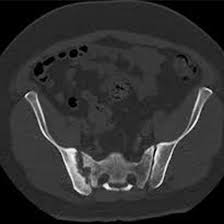

CT SI Joints

A CT SI Joints ( computed tomography sacroiliac) is a specialised examination used to create cross sectional images of the SI joints. This scan is really helpful in diagnosing many issues like lower back pain, leg pain, stiffness, swelling or tenderness in the SI joints, fractures, infections, and tumours.